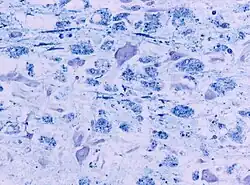

- Микроскопические изменения нервной ткани при осмотической демиелинизации

При гистологическом исследовании в очаге поражения отмечается не воспалительная демиелинизация, инфильтрация макрофагами и снижение количества олигодендроцитов за счет их апоптоза, астроглиоз и микроглиоз. При этом структура нейронов и аксонов сохранена.

Типичная локализация поражения в области моста может объясняться морфологической структурой данного региона, особенностью которого является высокая концентрация олигодендроцитов, компактное расположение и переплетение волокон серого и белого вещества. Схожая морфология есть и у регионов, которые могут вовлекаться в процесс вне моста. Это такие области головного мозга как мозжечок (поражается в 33 % случаев экстрапонтинного миелинолиза), наружная и внутренняя капсула, латеральное коленчатое тело, таламус, базальные ганглии и гиппокамп.[16]